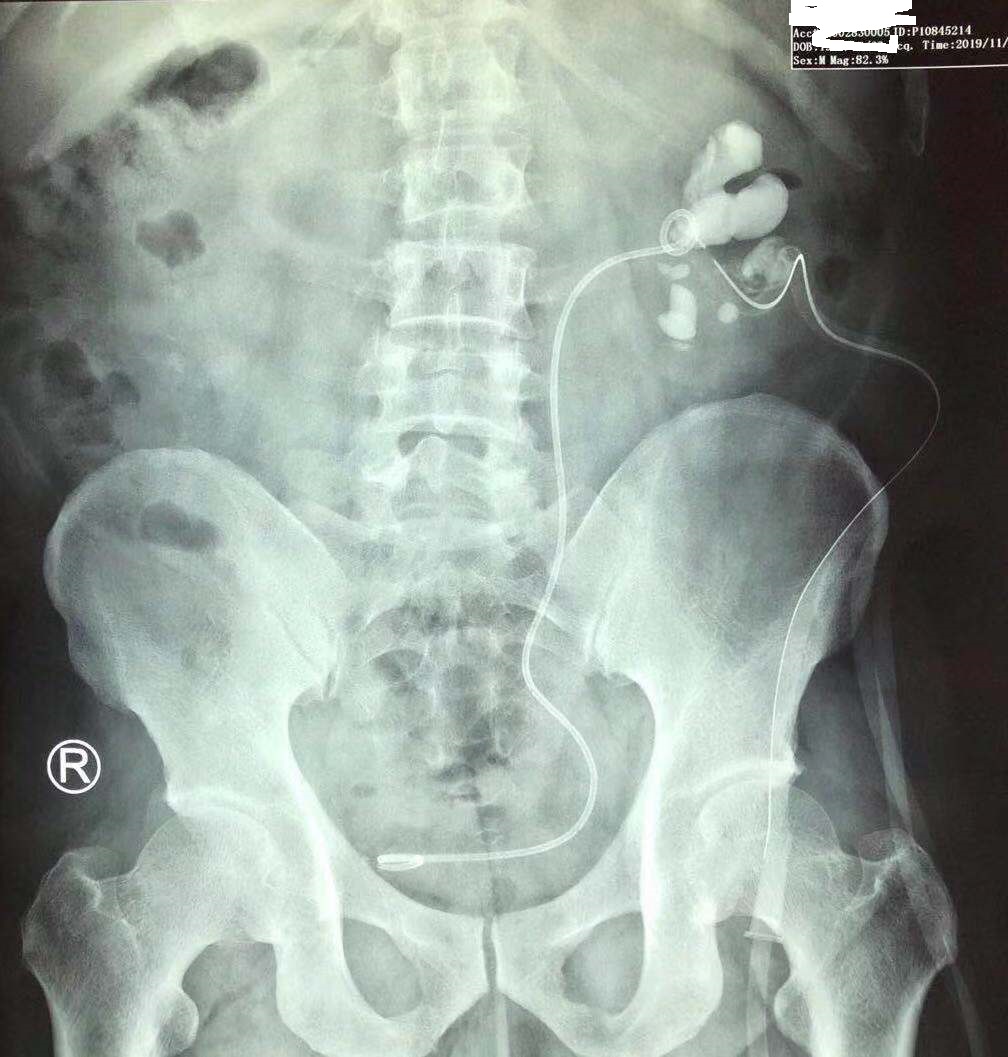

最后第三次手术把左侧肾脏剩下的50%结石彻底清除。这三次手术前后历时10天,最终把林先生的双肾鹿角形结石清除干净。

第三次手术取净左肾结石!